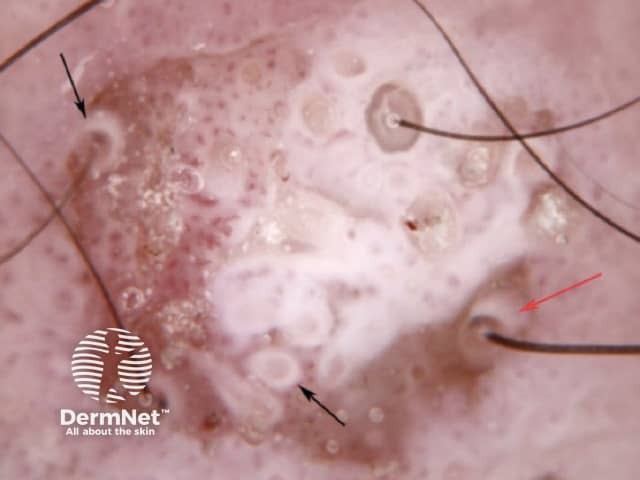

White structureless areas and white circles in squamous cell carcinoma dermoscopy

White circles in squamous cell carcinoma dermoscopy

White circles and surface keratin seen in squamous cell carcinoma dermoscopy

White structures and surface keratin in squamous cell carcinoma dermoscopy